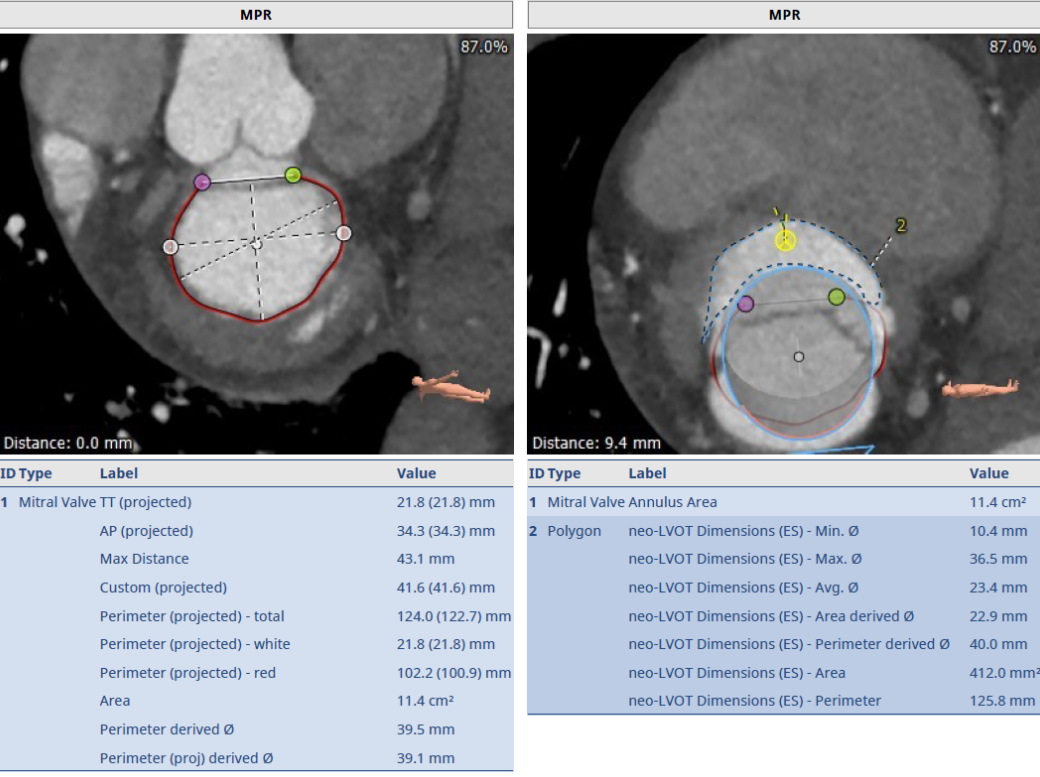

术前超声评估:

术前TTE超声提示二尖瓣大量反流